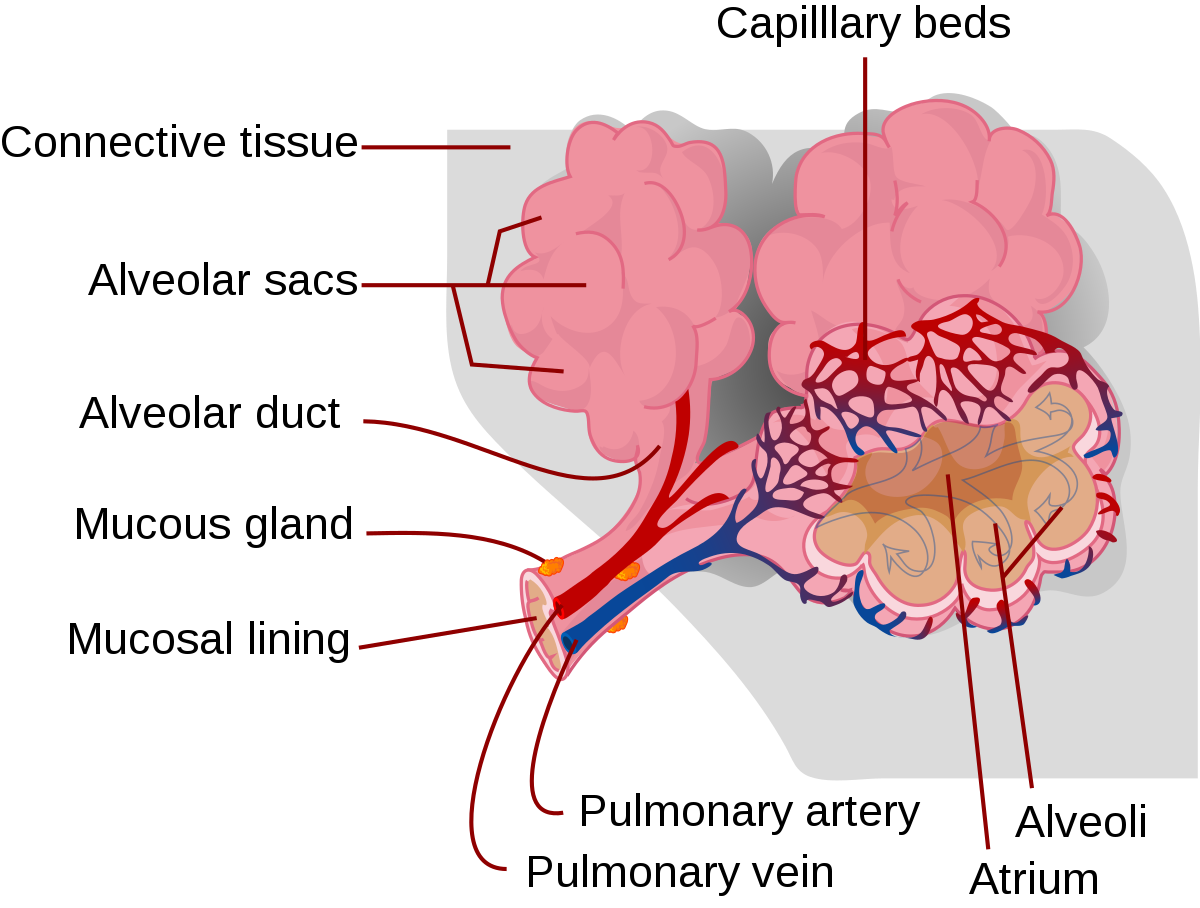

alveoli anatomy alveolus glands kenhub sac mammary

Lung anatomy & function. Alveoli bronchioles anatomy edu adapted. Organs and structures of the respiratory system